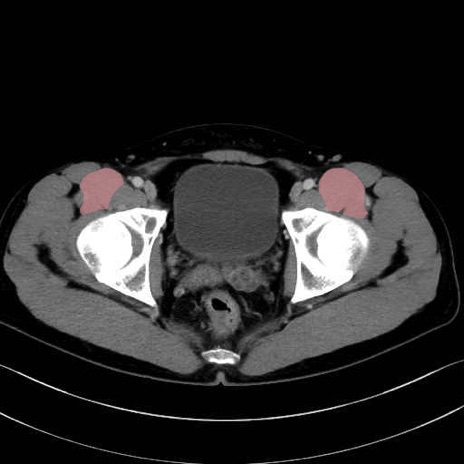

腸骨筋 (Iliacus)